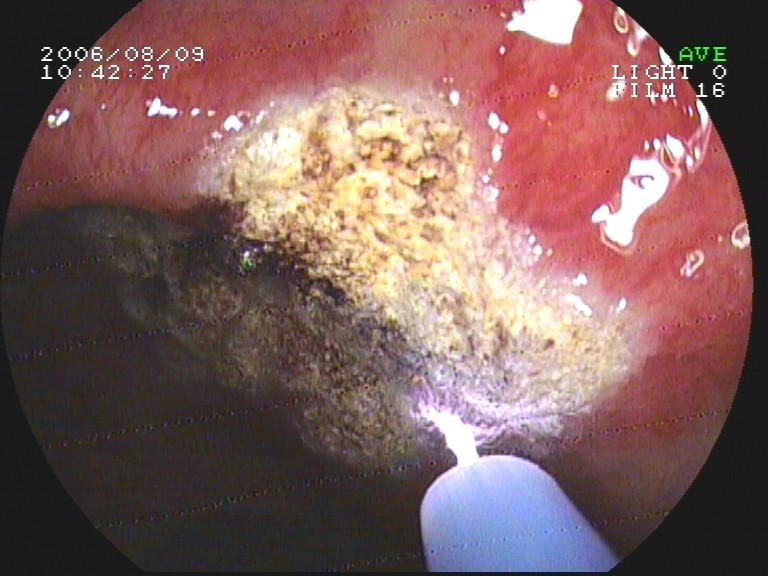

Coloskopie - Strahlenproctitis - APC-Therapie (Argonplasma-Koagulation)